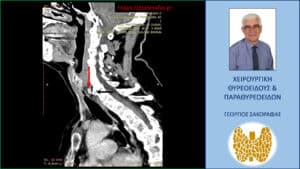

Λόγω επιμένοντος PHPT και με δεδομένους τους περιορισμούς των δύο βασικών διαγνωστικών εξετάσεων (υπερηχογράφημα και σπινθηρογράφημα) παραπέμφθηκε για περαιτέρω έλεγχο με τετραδιάσταση αξονική τομογραφία (4D-CT) όπου περιγράφεται μόρφωμα με διαστάσεις 9 x 7.5 x 5 mm παρά τον οισοφάγο, σε επαφή με την προσπονδυλική περιτονία, στο ύψος του Α6 σπονδύλου, πίσω από την τραχεία και την δεξιά κοινή καρωτίδα.

H εικόνα είναι συμβατή με έκτοπο αδένωμα παραθυρεοειδούς.

Έκτοπο αδένωμα παραθυρεοειδούς (κόκκινο βέλος)- απεικόνιση στην 4D-CT (προσθιοπίσθια διατομή). Το αδένωμα βρίσκεται σε επαφή με την προσπονδυλική περιοτονία (μαύρο βέλος)